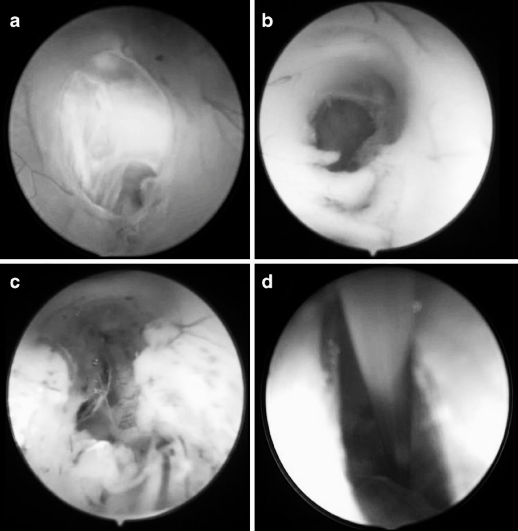

圖4 內(nèi)鏡下第三腦室的不同表現(xiàn),提示腦室解剖結(jié)構(gòu)日益扭曲。a. 被下丘腦粘連分為兩部分;b. 被下丘腦粘連分為兩部分,視野下方可見導(dǎo)水管;c. 被兩處下丘腦粘連分為三部分。

圖5 內(nèi)鏡下第三腦室底的不同表現(xiàn),導(dǎo)致實(shí)施 ETV(內(nèi)鏡第三腦室造瘺術(shù))難度遞增:a 呈水平狀、半透明且菲薄,可清晰辨認(rèn)漏斗隱窩;b 呈實(shí)質(zhì)樣,伴細(xì)薄下丘腦粘連;c 呈實(shí)質(zhì)樣,伴肥厚下丘腦粘連;d 呈實(shí)質(zhì)樣,伴肥厚下丘腦粘連及多條血管。

圖6 第三腦室底造瘺后的內(nèi)鏡解剖所見。a 多層膜結(jié)構(gòu);b 實(shí)質(zhì)樣腦室底下方為通暢的腦池間隙;c 實(shí)質(zhì)樣腦室底下方存在多條蛛網(wǎng)膜粘連帶;d 腦池深處僅見單一蛛網(wǎng)膜膜片,與實(shí)質(zhì)樣腦室底距離極遠(yuǎn)。